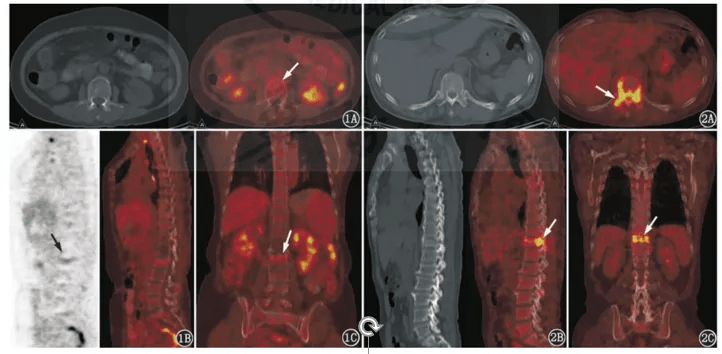

发布高建英主任petct在肿瘤远处转移中的临床应用